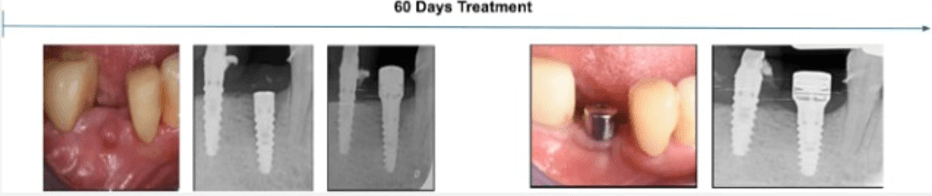

Patient Age: 35 Years.

Condition Treated: Localized Inflammatory environment

Treatment Duration: 60 Days.

Follow-Up: 2 Months

Case Summary: A 35-year-old female presented with a red, edematous bulge (2.5 mm diameter) two months after implant placement in site #45, previously extracted due to vertical root fracture. A periapical X-ray revealed early signs of bone loss at the coronal level, indicating inflammatory environment onset.

Treatment Approach: A Magdent MED healing abutment was placed for 60 days to deliver localized PEMF therapy and promote tissue regeneration around the implant.

Clinical Outcome:

• Inflammation and edema fully resolved

• Bone density and level significantly improved (confirmed via X-ray)

• Implant clinically stable and asymptomatic